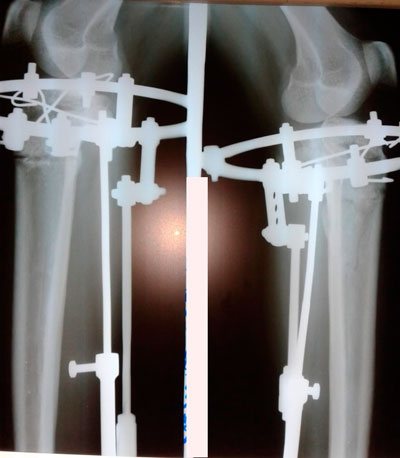

Исходник - 26 лет.

Дата операции - 08.05.2019г.

IMG_3131-12-05-19-07-39.JPG

IMG_3138-12-05-19-07-39.JPG